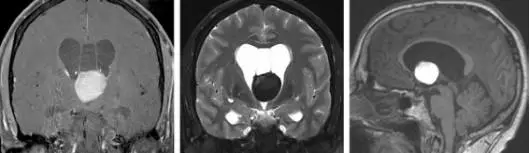

图1. MRI显示一个大的出血性胶样囊肿。透明间腔(第五脑室)的存在创造了穹窿间的潜在空间,这有利于穹窿间入路的使用。